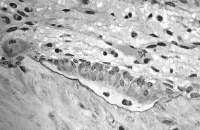

Disruption of such trabecular connections is known to occur preferentially in patients with osteoporosis, particularly in postmenopausal women, making females more at risk than males for vertebral compression fractures (see the images below).

Rosen and Tenenhouse studied the unsupported trabeculae and their susceptibility to fracture within each vertebral body and found an extraordinarily high prevalence of trabecular fracture callus sites within vertebral bodies examined at autopsy, typically 200-450 healing or healed fractures per vertebral body.[24] These horizontal trabecular fractures are asymptomatic, and their accumulation reflects the impact of lost trabecular bone and greatly weakens the cancellous structure of the vertebral body.

The reason for preferential osteoclastic severance of horizontal trabeculae is unknown. Some authors have attributed this phenomenon to overaggressive osteoclastic resorption.